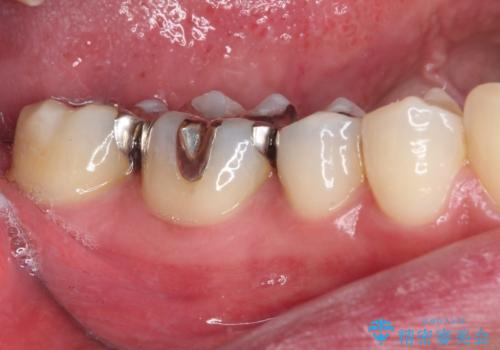

銀歯をセラミックにしたい セラミックインレー修復

- 銀歯をセラミックにしたいとのことで来院された患者様です。

まず麻酔をして銀歯を外し、むし歯を除去し、形を整えて型取りします。

そして次の来院時、セラミックインレーを装着し、噛み合わせなどの調整を行います。

それを左右に分けて行いました。

インレーを装着するときは、唾液や血液による接着力の低下を避けるためにラバーダム防湿を行いました。